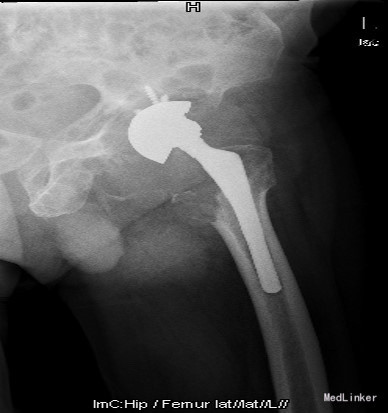

查体:左腹股沟区可见瘢痕及色素沉着,左腹股沟区可触及质硬包块,触之胀痛,局部皮温正常,左下肢内侧皮肤麻木。左髋外展10°,内收10°,屈曲80°,伸0°,内旋0°,外旋5°,右髋外展20°,内收15°,屈90°,伸0°,内旋10°,外旋10°,双髋内、外旋活动诱发疼痛;双下肢基本等长,双侧4字试验(+)。 辅助检查:双髋内、外旋活动诱发疼痛;双下肢基本等长,双侧4字试验(+)。X线片:左髋THA后假体向上移位,右侧股骨形态失常,关节间隙变窄

诊断:1.左侧THA术后假体松动、聚乙烯内衬磨损、炎性假瘤形成 2.左侧THA术后髋臼及股骨近端骨溶解 3.左侧THA术后髋臼及股骨近端骨缺损(髋臼AAOS III型 股骨Paprosky II型) 4.右髋重度骨关节炎 5.高血压 (2期 高危) 治疗:完善检查,调整患者全身条件后在全麻下行左侧全髋关节假体取出+炎性假瘤切除+异体骨植骨+髋臼重建+人工全髋关节翻修术,术中发现:左髋关节囊后外侧炎性假瘤形成,与关节腔相通,内有大量咖啡色混浊液体,髋臼及股骨近端骨溶解导致骨缺损,以髋臼前壁及下壁和股骨近端严重,小转子消失,关节腔周围大量炎性坏死组织。髋臼假体松动。术中安放左侧Zimmer64mmCage,并用8枚不同长度螺钉固定可靠,Cage内放骨水泥后安放外径59mm,内径28mm聚乙烯内衬并调整前倾及外展角度合适,股骨侧安放12#加长股骨柄,28mm直径、+1.5颈长陶瓷股骨头。